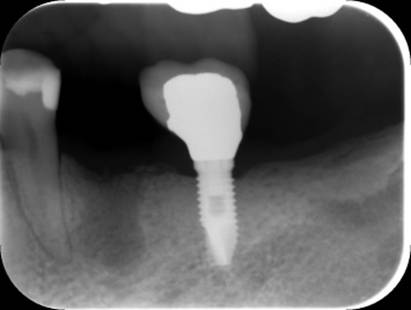

術後のCBCT

インプラントの重大な事故は下顎管から十分な距離をとれば防げます

抜歯部位にインプラントを追加しました。CBCT